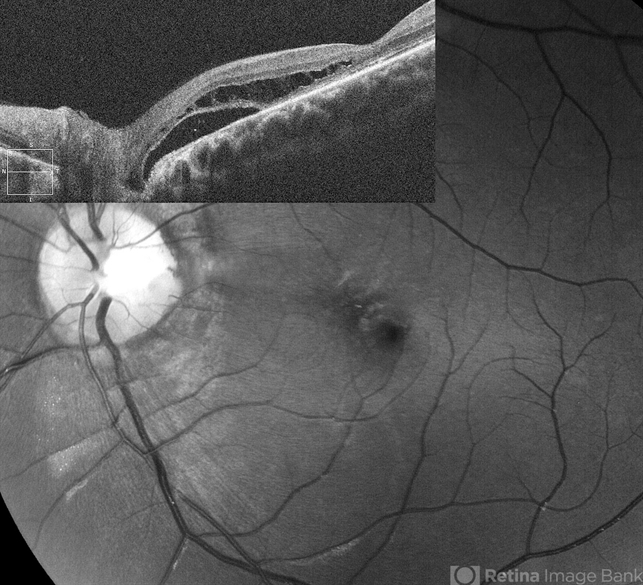

- optic disc pit

- Optic disc pit with peripapillary RD and macular schisis, fundus photograph and SD-OCT overlay.